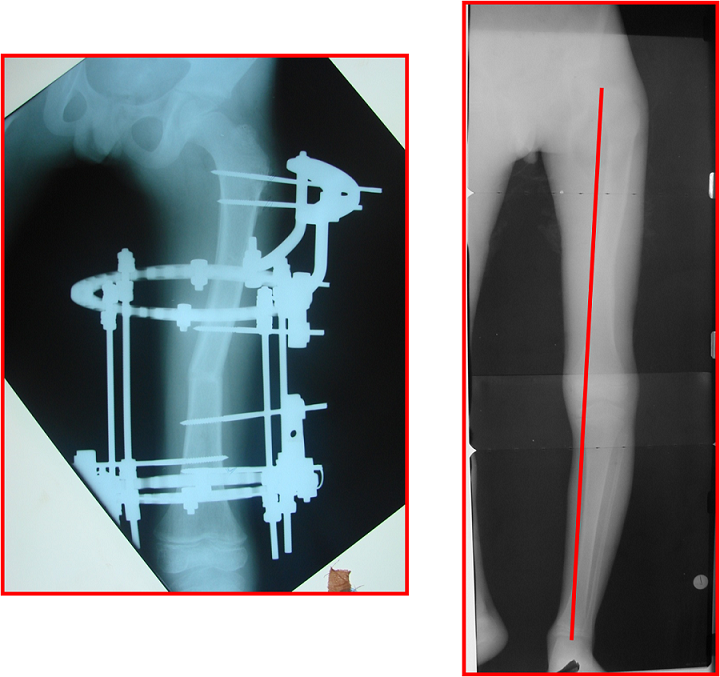

arthritis deformity surgery endoprosthesis hip prosthesis ilizarov ilizarov surgery infected nonunion knee prosthesis lengthening surgery limb lengthening surgery nonunion periprosthetic infection psodoartroz revision surgery total hip prosthesis total knee prosthesis